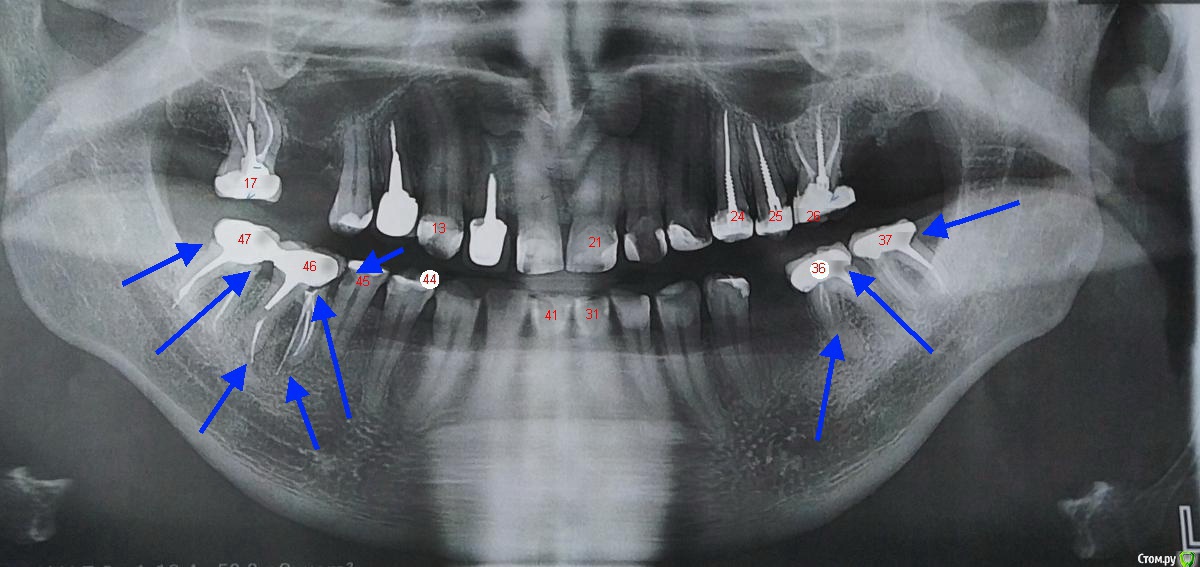

Bier Опубликовано 1 августа, 2020 Поделиться Опубликовано 1 августа, 2020 ещё один?так и не понял про какой речь вот я вам проставил номера, чтобы было понятнее 1 Ссылка на комментарий

Bier Опубликовано 1 августа, 2020 Поделиться Опубликовано 1 августа, 2020 вот так еще понятнее 2 Ссылка на комментарий

Ljocha Опубликовано 1 августа, 2020 Автор Поделиться Опубликовано 1 августа, 2020 Bier теперь совсем все понятно!огромное спасибо! 46 особо интересен, так как лечил 2 месяца назад и там по словам стоматологов никаких осложнений не было,вынули штифты, перелечили все каналы, поставили коронки - со слов никаких проблем,потом на частном приеме от врача который перелечивал, по секрету узнал что такой просвет это совсем не дело, считаете что по гарантии снять коронку, заделать просвет и вновь поставить коронку нельзя? Ссылка на комментарий